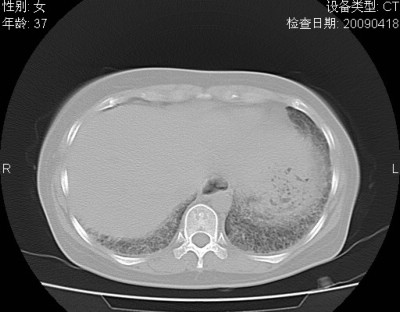

以下是引用随光逐影在2009-4-20 8:03:00的发言:[br]两肺间质性病变(间质性肺炎?特发性肺间质纤维化?)。

以下是引用51736011在2009-4-21 16:24:00的发言:[br]两肺间质性病变(间质性肺炎?特发性肺间质纤维化?)。